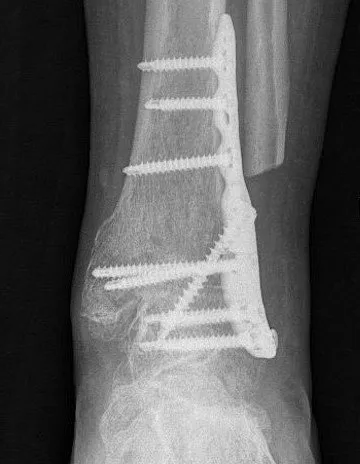

Ankle fusion is permanently stiffening the bones of the ankle together with plates and screws. This procedure is also known ankle arthrodesis.

Dr Beamond performs ankle fusion using three techniques (see images below):

- lateral open ankle fusion.